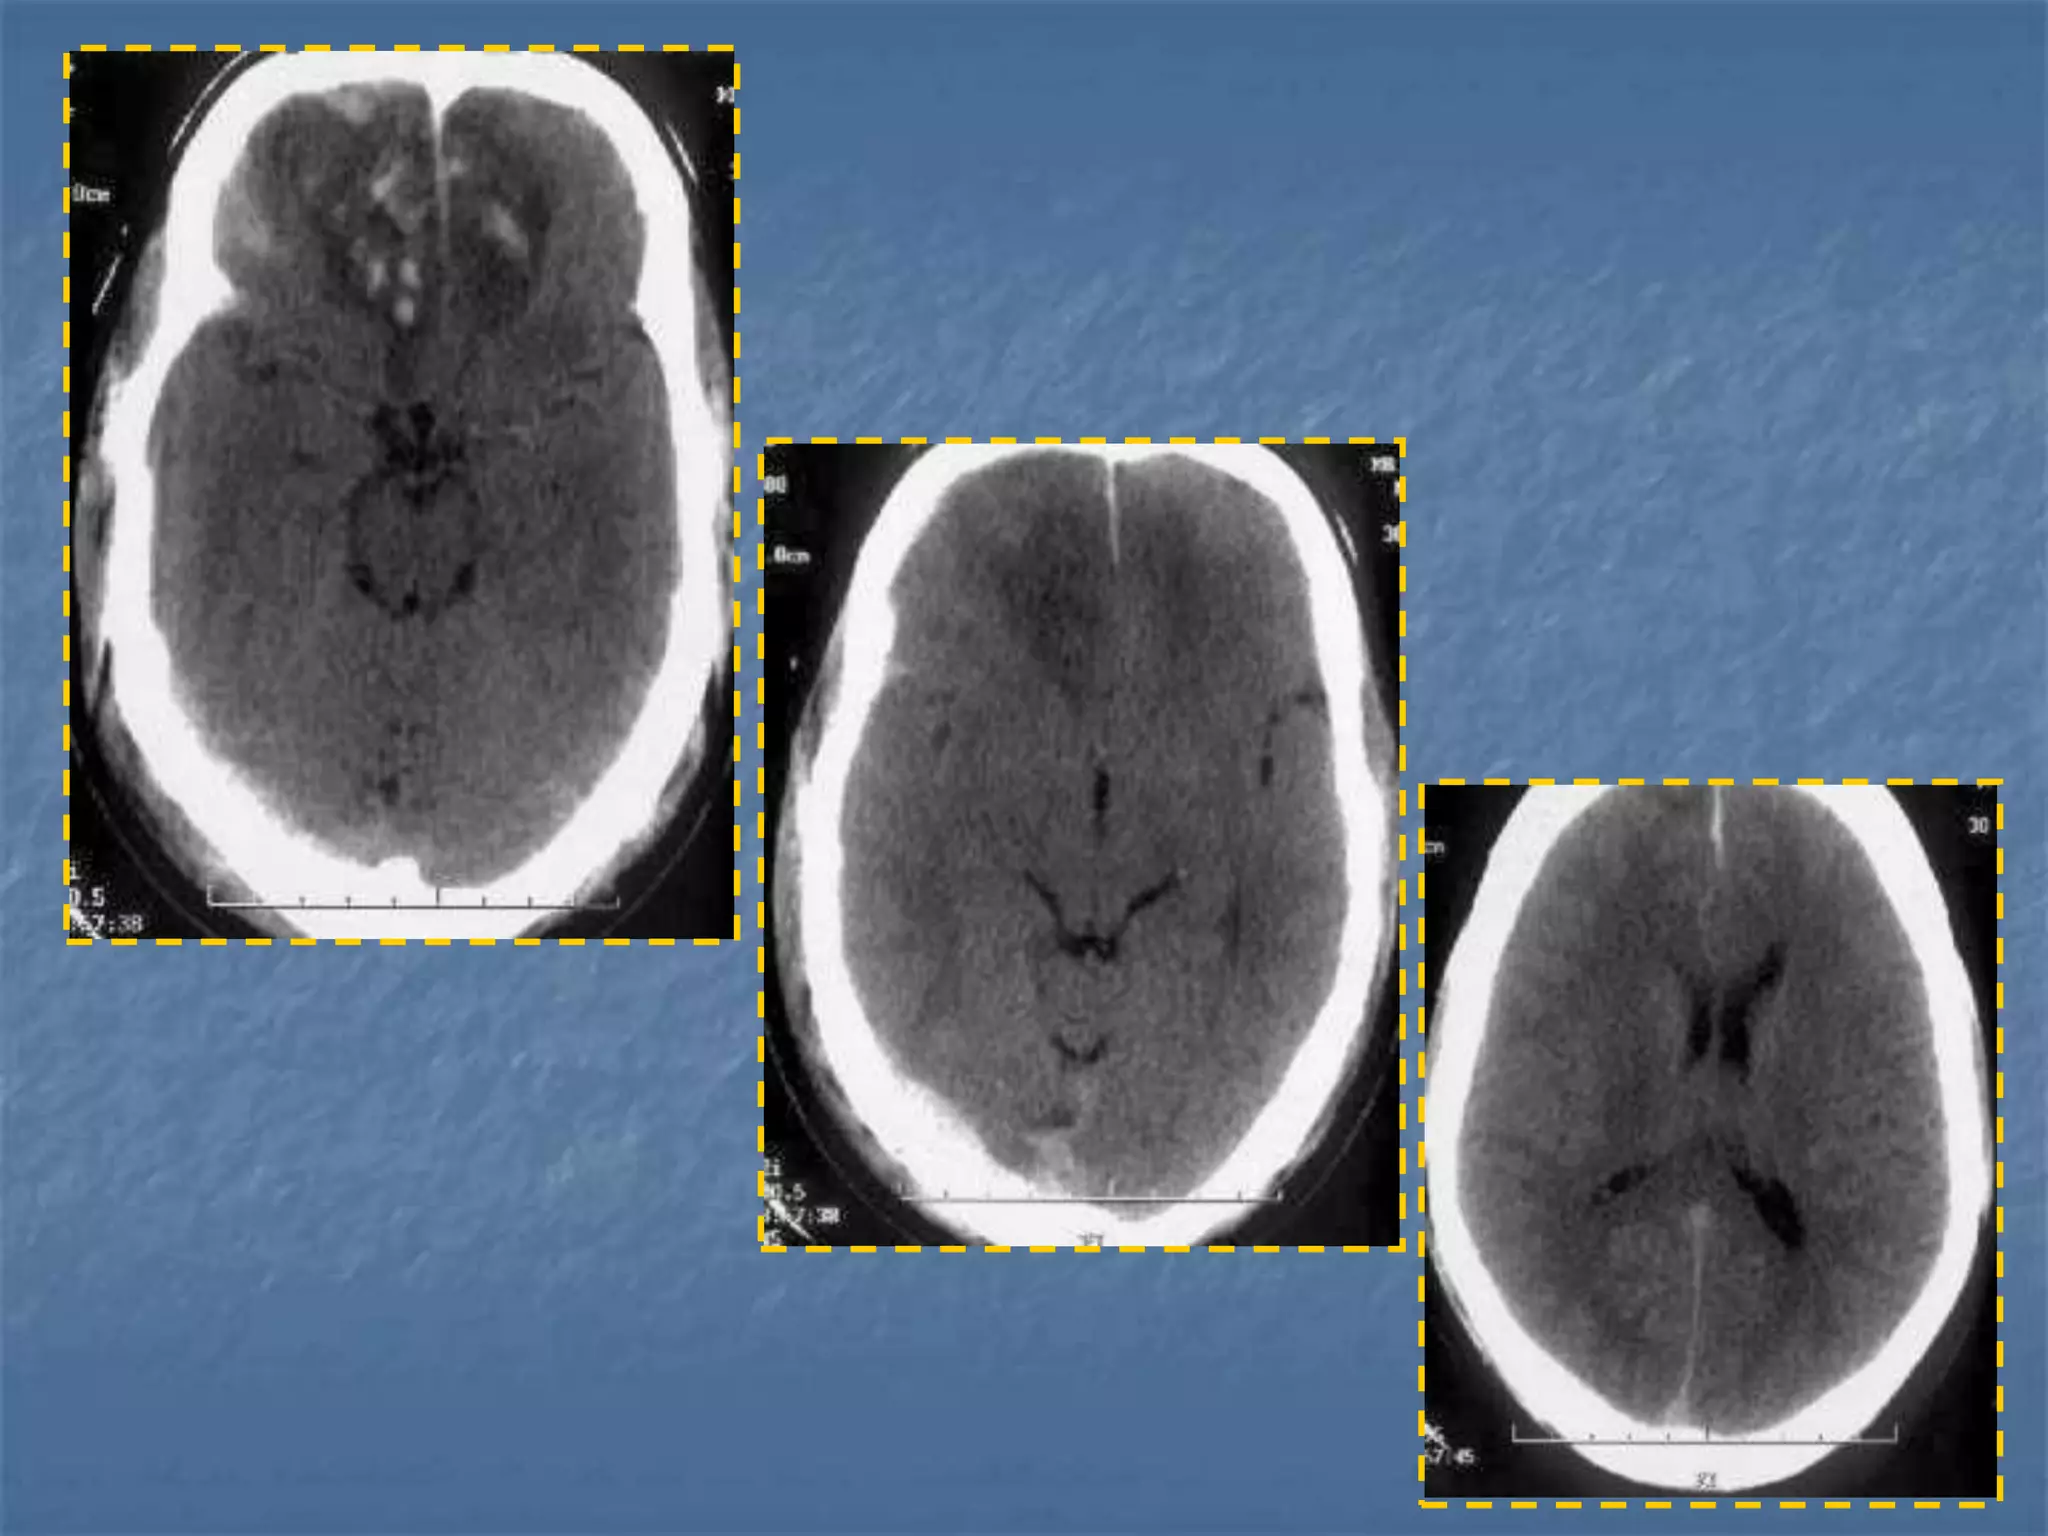

Hypertensive Hemorrhage

 Hypertensive hemorrhage accounts for

approximately 70-90% of non-traumatic primary

intracerebral hemorrhages. It is commonly due to

vasculopathy involving deep penetrating arteries

of the brain. Hypertensive hemorrhage has a

predilection for deep structures including the

thalamus, pons, cerebellum, and basal ganglia,

particularly the putamen and external capsule.

Thus, it often appears as a high-density

hemorrhage in the region of the basal ganglia.

Blood may extend into the ventricular system.

Intraventricular extension of the hematoma is

associated with a poor prognosis.

Diffuse Axonal Injury

 Diffuse axonal injury is often referred to as "shear injury". It is the most

common cause of significant morbidity in CNS trauma. Fifty percent of all

primary intra-axial injuries are diffuse axonal injuries. Acceleration,

deceleration and rotational forces cause portions of the brain with

different densities to move relative to each other resulting in the

deformation and tearing of axons. Immediate loss of consciousness is

typical of these injuries. The CT of a patient with diffuse axonal injury may

be normal despite the patient's presentation with a profound neurological

deficit. With CT, diffuse axonal injury may appear as ill-defined areas of

high density or hemorrhage in characteristic locations. The injury occurs in

a sequential pattern of locations based on the severity of the trauma. The

following list of diffuse axonal injury locations is ordered with the most

likely location listed first followed by successively less likely locations:

- Subcortical white matter

- Posterior limb internal capsule

- Corpus callosum

- Dorsolateral midbrain